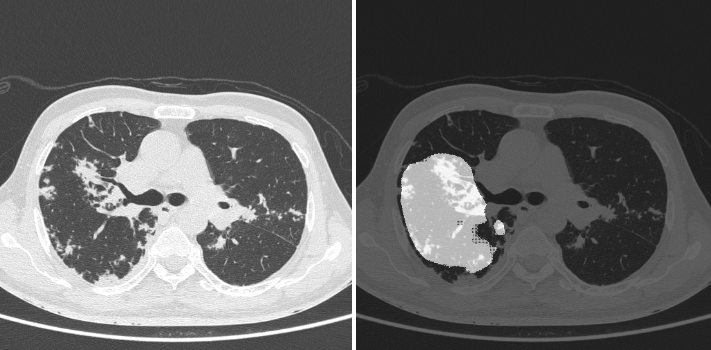

We tested our model using varied sets of data from different sources. We initially evaluated the model on our test set, consisting of 1330 images, in which COVID-19-positive samples had a prevalence of 20%. Our model gave a sensitivity of 0.963 (95% CI: 0.94-0.98) and a specificity of 0.936 (95% CI: 0.92-0.95). The dice coefficient on positive samples was 0.561. figures 2 and 3 show the superimposed masks on one of the slices.

Refer to caption

Figure 3: (Left) original image and (right) corresponding predicted mask.